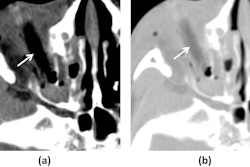

Chest x-rays with anteroposterior and lateral views are the primary method for detecting these foreign objects, with CT and MRI recommended in cases of suspected tissue damage.

"Though data are limited, imaging with MRI currently offers the best modality to comprehensively assess the evolution of tissue injury and involvement of associated structures," the authors wrote.